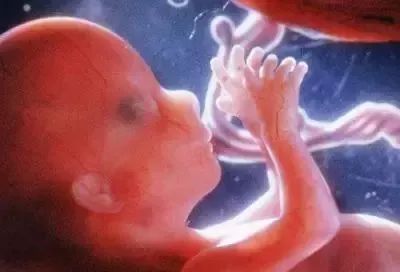

受精卵吸收母亲提供的营养物质,细胞迅速分裂、增殖和发育。一些细胞形成胚胎并发育成胎儿;细胞的另一部分形成胎儿膜、羊水、脐带和胎盘,称为胎儿附属物,以确保胎儿的发育。

胎儿生长在子宫内,胎儿膜充满羊水。胎儿脐带由脐带与胎盘相连。胎儿生长所需的营养是通过胎盘从母亲身上获取的。

一个月:它标志着胚胎期的开始。身体长约0.2厘米,重约1克。受精卵裂变形成桑椹胚,并继续分裂成囊胚和着床。每个月,新生命的生长速度比任何时候都快,比受精卵高一万倍。动脉和静脉已经形成,并有血液流动;大脑、肾脏和消化道已经开始形成;脐带已经开始工作;心脏已经形成并开始跳动。